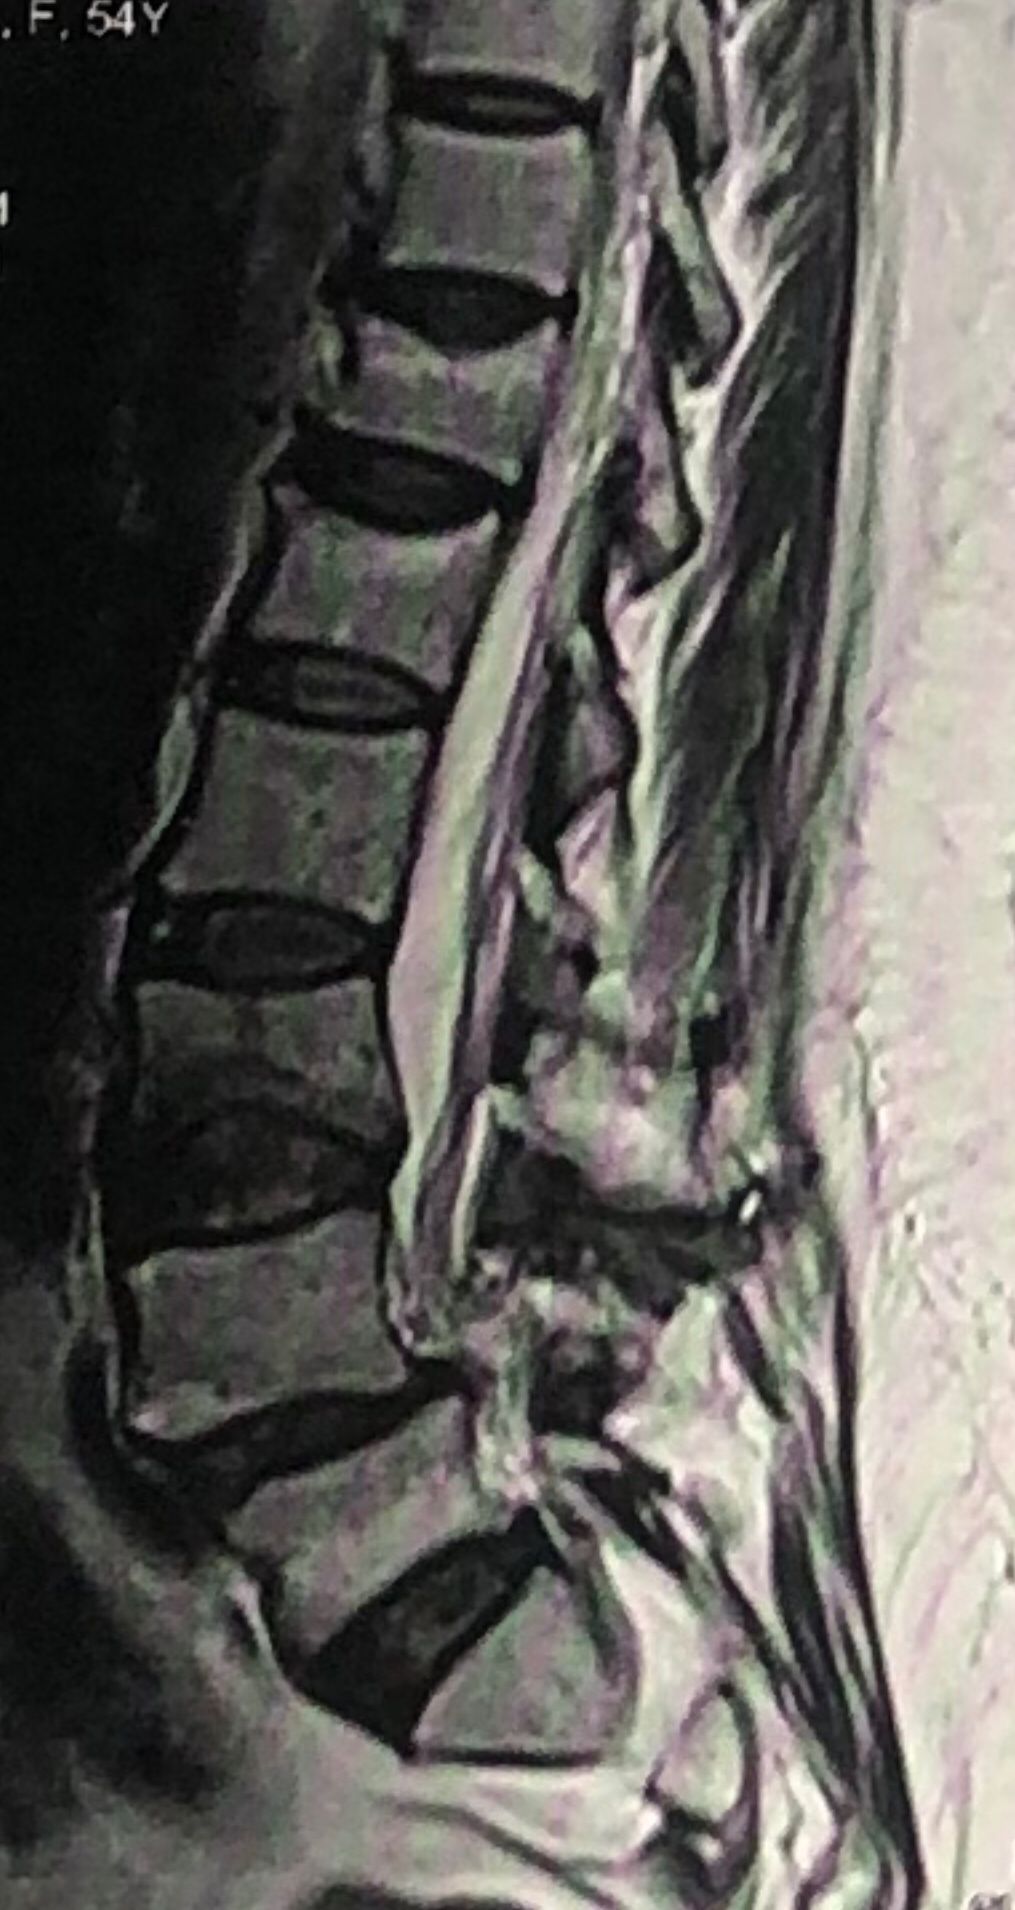

46 years old female patient presented to my clinic yesterday june 1/2025 with LBP and radicular L leg pain for several months which hasn’t responded to physio 2 neurosurgeons have visited her and didn’t suggest any surgery Neurological exam was unremarkable please see her mri/ emg/ncv and her huge tarlov cyst and possible L IVF L4-5 hyperbulge I ordered sacrum mri and ct scan and new emg/ncv and asked her with her sacral Ct scan and MRI first sees another two famous neurosurgeons and see if that large cyst is the reason for her pain if not i can work on her L4-S1 area Do you think her radicular pain can originate from her large cyst in sacrum? Do you consider surgery and removing her sacral cyst?